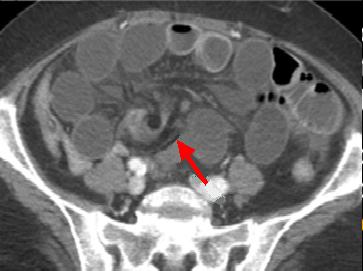

| L'occlusion par bride et

adherence represente de 50% des occlusions

intestinales . Aspect TDM particuliairement est

image de bec des oiseaux ( fleche rouge ) au niveau

de l'obtacle . Image de distension de l'intestin sus

- lesionelle et image hydro-aerique transitionnel .

L'intestin sous -lesionelle est collabe totale |

Image TDM en coupe

sagitale : Occlusion de l'intestin aigue avec

signe de bec de oiseaux ( fleche rouge ) et

dilatation intestinale en amont et signe de feces (

retention de feces au niveau de l'intestin sus -lesionelle |